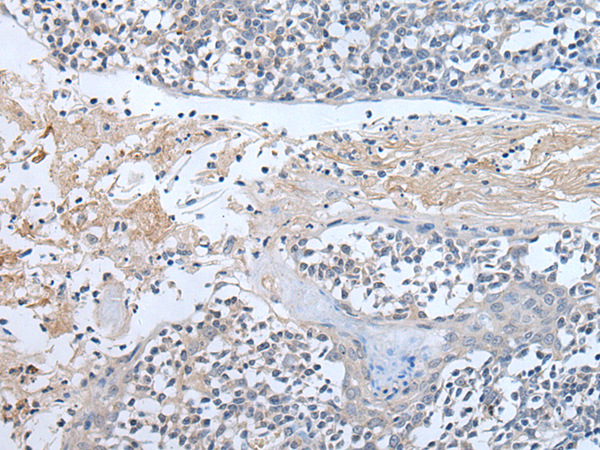

IHC positive control: |

Human tonsil |

IHC Recommend dilution: |

30-150 |